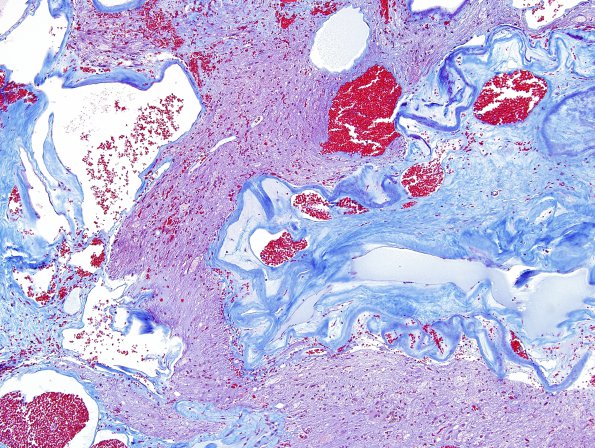

20C1 Cavernous angioma (Case 20) Trichrome 2

20C1-3 Trichrome staining of vasculature demonstrates marked fibrosis.